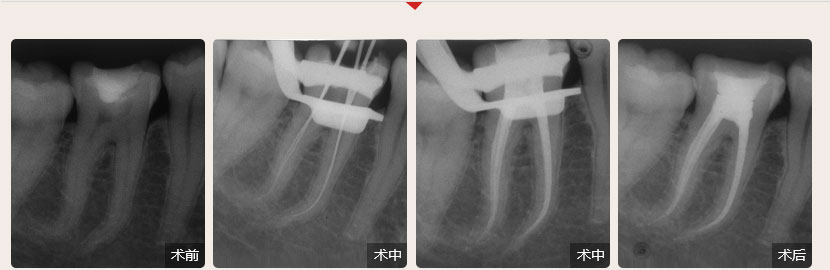

性別:男        年齡:55歲

牙齒癥狀:急性牙髓炎(左下牙自發性、陣發性痛3天)        治療方法:顯微根管治療

疑難點評:操作方面使用根管顯微鏡和超聲波系統細致尋找和定位根管,根管的敞開度較為完美,維持了根管的原有走向,充填致密,流暢,充填長度準確。

順德德倫口腔醫生全國根管治療技術競賽案例